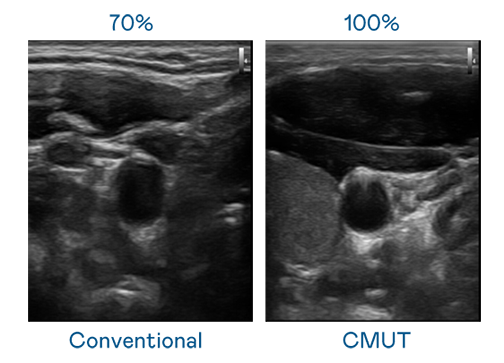

CMUT 技术是一种用电容式微机电元件来产生超音波讯号的技术。与传统 PZT 压电式技术相比,CMUT 频宽增加 30%,更宽频的超音波讯号让影像解析度大幅提升,是实现高影像品质医疗超音波扫描、促进精准医疗发展的关键技术。

大频宽带来超清晰影像

超音波影像的解析度高低,首先取决于探头能发出的讯号频宽。太阳集团7237 CMUT 可提供高清晰的超音波讯号,提供高频宽、高灵敏度、影像纹理细节更高的超音波影像,协助医护人员缩短影像判读时间及利用精准的医疗影像进行诊断。